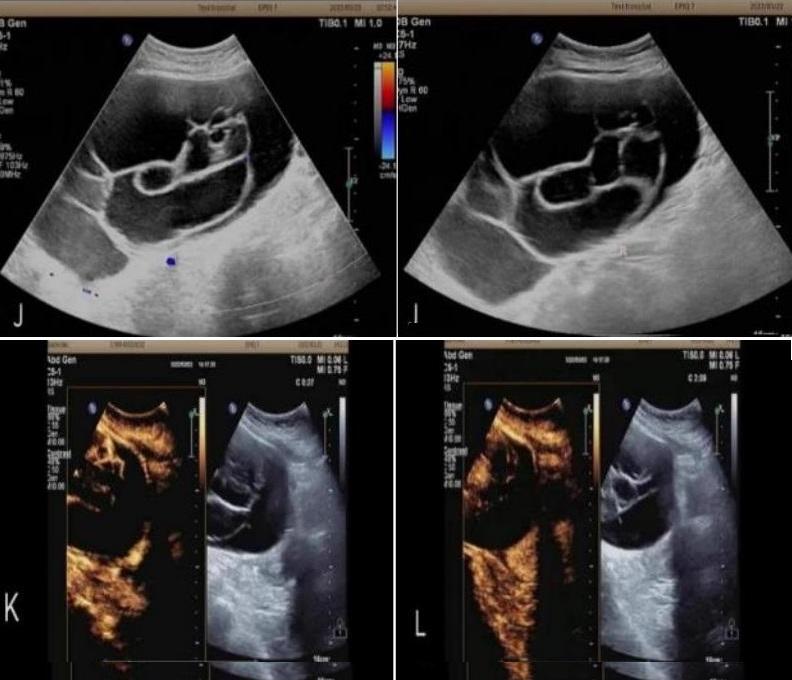

病例3:女,73岁,主因“下腹部触痛、外阴疼痛一周”入院。常规超声:子宫右前方囊性包块,其内可见粗细不等的分割,范围约17.1x10.0cm。静脉超声造影:增强早期囊壁及囊内分隔上可见造影剂灌注显影早于子宫肌层,达峰时囊壁及分隔上灌注区域呈高增强,增强晚期,囊壁及分隔上造影剂消退迟于子宫肌层,呈持续性低增强。超声造影提示:左卵巢粘液性囊腺瘤(可疑交界性)。术后病理:左卵巢粘液性囊腺瘤(局灶区域呈上皮样增生)。